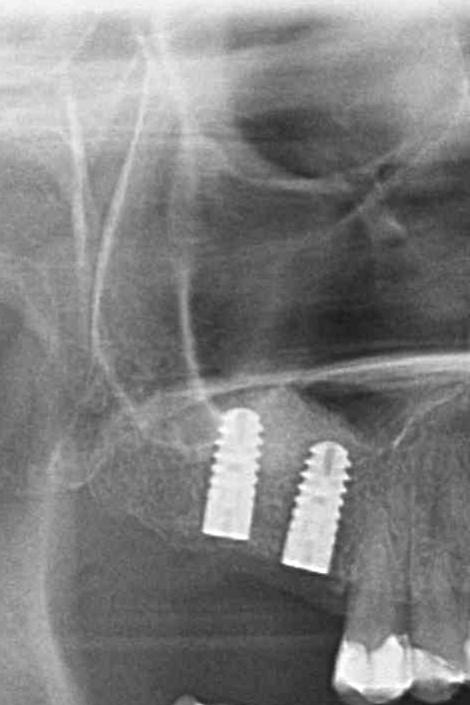

Nun habe ich mir das Röntgenbild auch mal angeschaut und sehe bei dem Zahn 16 (das rechte Implantat beim draufschauen) einen schwarzen Rand um das Implantat…..

Sieht es denn wirklích so perfekt aus oder ist das Implantat doch nicht so ganz perfekt in den Knochen eingewachsen??

Nun habe ich mir das Röntgenbild auch mal angeschaut und sehe bei dem Zahn 16 (das rechte Implantat beim draufschauen) einen schwarzen Rand um das Implantat…..

Hätte ich nicht schon soviel über schwarze Ränder um Implantate gelesen und wie böse das ausgehen kann, würde ich mir keine Sorgen machen, denn “mein” Kieferchirug sagte alles sähe perfekt aus! Sieht es denn wirklích so perfekt aus oder ist das Implantat doch nicht so ganz perfekt in den Knochen eingewachsen??

Es schaut alles ok aus, aber nicht perfekt. Das letzte Implantat steht vermutlich ein wenig in die Kieferhöhle und ist nicht vom Knochen umgeben – perfekt wäre es, wenn es eben vom Knochen umgeben wäre. Das passiert aber manchmal, ist mir auch schon passiert. Trotzdem halten auch diese Implantate „100 Jahre“, also kein Grund für eine weitere Therapie.

Wichtig sind 1/2 jährliche Röntgenbildkontrollen in den ersten 2 Jahren, wenn es in den ersten 2 Jahren stabil ist, dann wird es vermutlich auch weiterhin stabil bleiben, wenn nicht, dann müsste man z.B. nach augmentieren (ist aber sehr selten notwendig). Das Schlimmste was passieren könnte ist, z.B. bei einer schweren Nasennebenhöhlenentzündung, dass sich das Implantat infiziert – das wäre aber ein Lotto Sechser, sowie die postulierte HIV Infektion bei einem Gelsenstich … als Redewendung zu verstehen – [URL=”http://www.checkdent.com/dental-blog/aids-eine-erfundene-seuche.html?lang=de”]unabhängig davon jetzt, dass HIV nicht AIDS verursacht[/URL] …

Zugewachsen ist auch vermutlich … also mit Schleimhaut, aber eben nicht mit Knochen, aber in der Regel macht das nix …